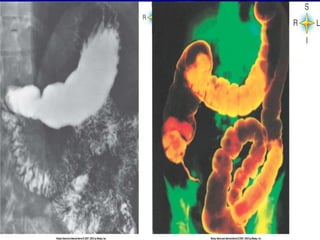

Intestino Grueso Dimensiones del intestino grueso—diametro promedio es de 6 cm y su longitud es de aproximadamente 1.5-1.8 m Divisiones del intestino grueso  Cecum o ciego—primeros 5-8 cm,saco ciego en el cuadrante inferior derecho  Colon Colon ascendente—esta en posicion vertical en el lado derecho del abdomen extendiendose hasta el borde inferior del higado(angulo hepatico); la valvula ileocecal permite el paso del material del ileon al intestino grueso pero no en sentido contrario Colon transverso --cruza horizontalmente el abdomen por debajo del higado, estomago y bazo (angulo esplenico) pero por encima del intestino delgado. Se extiende desde el angulo hepatico hasta el angulo esplenico Colon descendente—esta en posicion vertical en el lado izquierdo del abdomen,por debajo del bazo hasta el nivel de la cresta ileaca Colon sigmoide—une el colon descendente al recto Rectum—ultimos 17-20 cm (7-8 pulgadas) del tracto GI;los ultimos 2.5cm del recto constituyen el canal anal y la apertura del conducto al exterior es el ano

Intestino Grueso Dimensionesdel intestino grueso—diametro promedio es de 6 cm y su longitud es de aproximadamente 1.5-1.8 m Divisiones del intestino grueso Cecum o ciego—primeros 5-8 cm,saco ciego en el cuadrante inferior derecho Colon Colon ascendente—esta en posicion vertical en el lado derecho del abdomen extendiendose hasta el borde inferior del higado(angulo hepatico); la valvula ileocecal permite el paso del material del ileon al intestino grueso pero no en sentido contrario Colon transverso --cruza horizontalmente el abdomen por debajo del higado, estomago y bazo (angulo esplenico) pero por encima del intestino delgado. Se extiende desde el angulo hepatico hasta el angulo esplenico Colon descendente—esta en posicion vertical en el lado izquierdo del abdomen,por debajo del bazo hasta el nivel de la cresta ileaca Colon sigmoide—une el colon descendente al recto Rectum—ultimos 17-20 cm (7-8 pulgadas) del tracto GI;los ultimos 2.5cm del recto constituyen el canal anal y la apertura del conducto al exterior es el ano